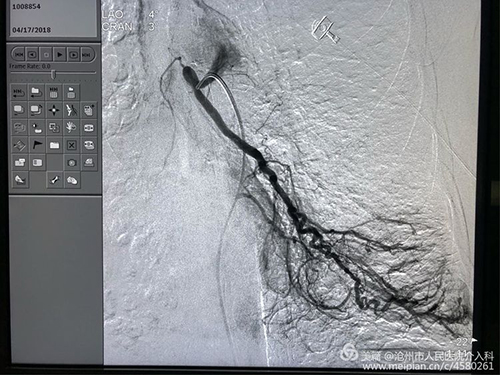

患者女性,67岁,大咯血,重度支气管扩张并感染、肺结核、肺气肿病史30余年,并肺动脉高压、肺心病、右心衰。曾于县、市多家医院及北京协和医院多次治疗心肺功能极差,外院应用止血药物无效,转入我科。下图为术前CT急诊行介入治疗,术中造影可见双侧支气管动脉均异常粗大,是出血的罪犯血管。栓塞后患者咯血即停止,效果立竿见影。

左侧病变支气管动脉